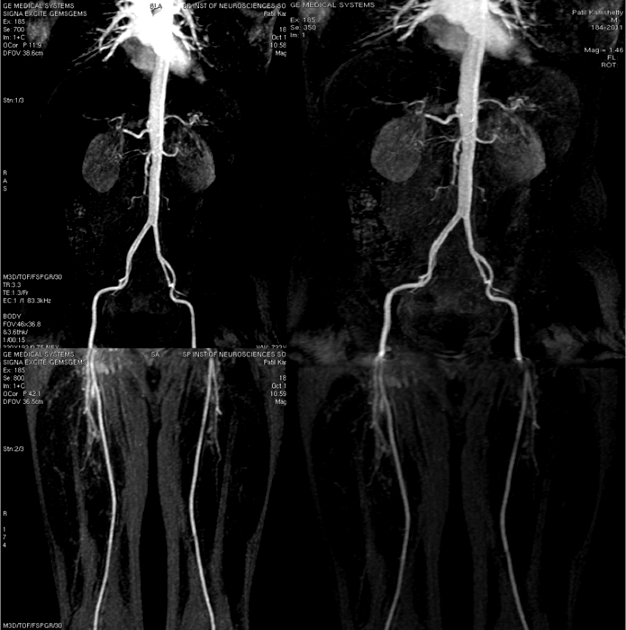

From spinradiographers.blogspot.com

SPIN RADIOGRAPHERS Contrastenhanced MR angiography of abdominal aorta What Is A Mri Angiography A regular angiogram requires inserting a thin tube. An mra can detect narrowing or. In magnetic resonance angiography (mra), a powerful magnetic field, radio frequency waves and a computer are used to evaluate blood. It looks just at the body’s blood vessels. Magnetic resonance angiography (mra) encompasses several imaging techniques based on magnetic resonance imaging (mri) developed for studying the.. What Is A Mri Angiography.